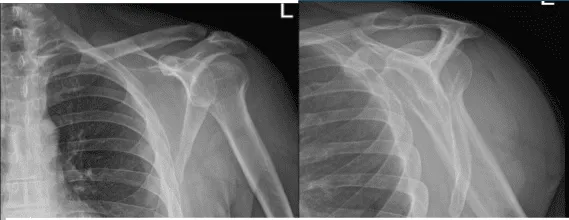

Se presentaron radiografías del hombro derecho e izquierdo. En el hombro derecho no hubo fracturas agudas, aunque hay un ensanchamiento asimétrico de la articulación acromioclavicular del hombro derecho y, para una evaluación adicional, se recomienda correlacionarse con la resonancia magnética. Por otro lado, la radiografía del hombro izquierdo mostró radiografías normales.

Radiografía del hombro derecho

Radiografía del hombro izquierdo